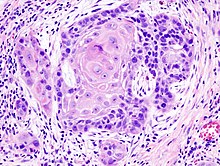

_squamous_cell_carcinoma_histopathology.jpg)

Squamous cell cancers are common in areas of the mouth, including the inner lip, tongue, floor of mouth, gums, and hard palate. Cancers of the mouth are strongly associated with tobacco use, especially use of chewing tobacco or dipping tobacco, as well as heavy alcohol use. Cancers of this region, particularly the tongue, are more frequently treated with surgery than are other head and neck cancers.

A person usually presents to the physician complaining of one or more of the above symptoms. The person will typically undergo a needle biopsy of this lesion, and a histopathologic information is available, a multidisciplinary discussion of the optimal treatment strategy will be undertaken between the radiation oncologist, surgical oncologist, and medical oncologist.[medical citation needed] Most ( 90%) cancers of the head and neck are squamous cell-derived termed as "head and neck squamous-cell carcinomas".[6]

Squamous-cell carcinoma is a cancer of the squamous cell – a kind of epithelial cell found in both the skin and mucous membranes. It accounts for over 90% of all head and neck cancers,[49] including more than 90% of throat cancer.[15] Squamous cell carcinoma is most likely to appear in males over 40 years of age with a history of heavy alcohol use coupled with smoking.